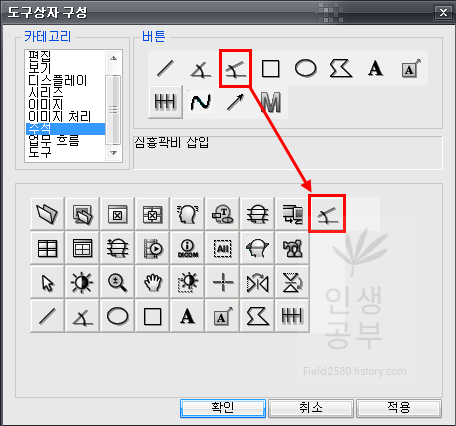

저 같은 경우는 Cobb 각도를 많이 사용하기 때문에 우선 Cobb각도 설정하는 방법에 대해서 알려드리겠습니다. 카테고리칸에 주석을 눌러주면 다양한 각도나 선, 모양을 그릴 수 있는 버튼이 나옵니다. 그중 상단 3번째 있는 버튼이 Cobb각도 그리기 입니다.

Cobb각도 그리기 버튼을 클릭해주고 아래로 쭉 내려주면 현재 사용하고 있는 도구상자에 Cobb각도 그리기 버튼이 추가되는 것을 확인하실 수 있습니다.